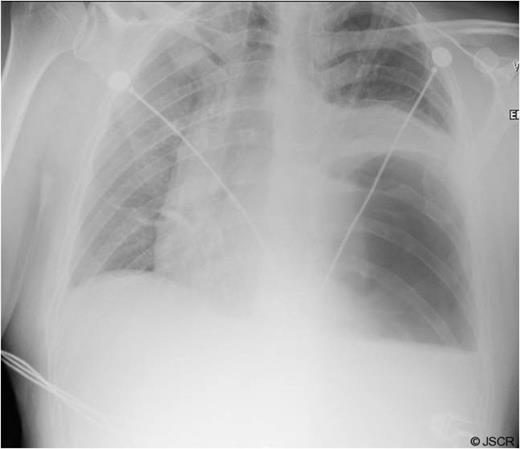

Chest pain persisted and the patient required higher pressure CPAP to maintain adequate oxygenation. Auscultation consistently showed decreased air-entry in the lung bases. On day 3, a repeat chest x-ray showed a left lower lobe collapse above the gastric bubble in the mid zone of the chest (Fig. 4 & 5). CTPA done on the same day to exclude pulmonary embolism confirmed a para-oesophageal hernia that was pushing against the left lung base. Ultrasound scan of the left chest also showed movement of the diaphragm below the gastric bubble.

Chest x-ray on 3rd post-op day showing prominent left sided collapse/ consolidation

Post-op CT-scan demonstrating the left sided pleural effusion with collapse /consolidation & patchy opacification on the right side.